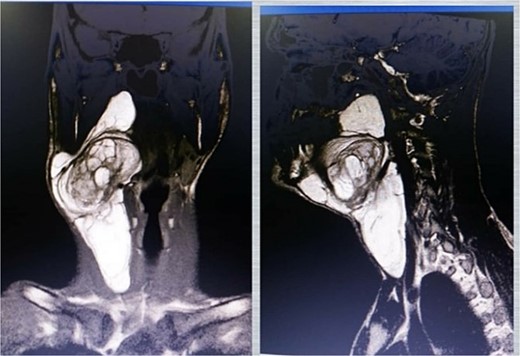

A neck ultrasound revealed a well-defined, solid, mildly hyper-echoic, heterogeneous subcutaneous mass located on the right side of the neck. A contrast-enhanced MRI scan showed a 14 cm diameter, well-demarcated, high-signal, non-homogeneous mass adjacent to the carotid artery and thyroid gland (Figs 1 and 2). The radiologist suggested lipoma as the most probable diagnosis. Ultrasound-guided fine-needle aspiration (FNA) of the mass identified some lipocytes and fibrocytes but no malignant cells.

T2-weighted MRI image showing the relationship between the mass and the carotid sheath (indicated by the arrow).